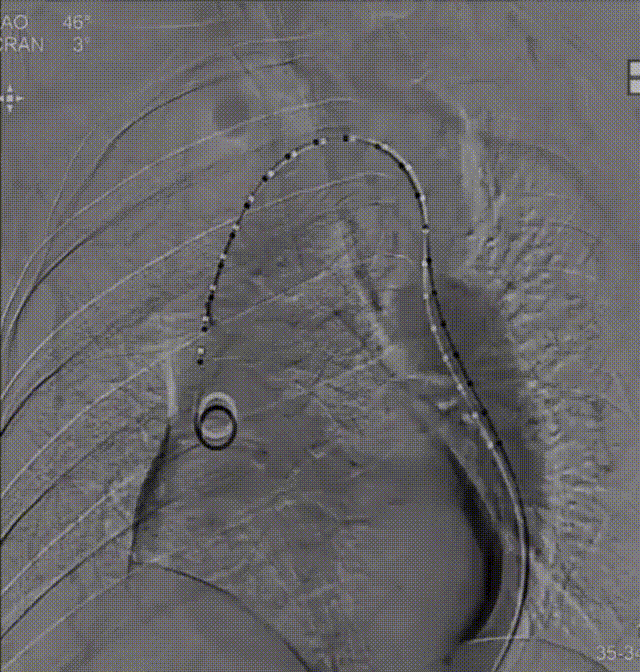

术中考虑到患者心功能极差,为避免全麻过程中患者循环崩溃,遂采用局麻强化策略;同时由于患者髂动脉内曾植入支架,因此选择左侧股动脉作为主、副入路。经左侧股动脉入路成功穿刺后,首先置入20 F大鞘,并于大鞘中置入一个5 F鞘管和一个10 F鞘管。成功沿10 F鞘管送入导丝,完成跨瓣操作后,随后沿导丝送入20 mm球囊进行预扩张,并于主动脉根部造影。造影结果显示,预扩球囊腰征明显且无瓣周漏,遂选择TaurusElite 23 mm可回收瓣膜。

由于是采用单血管入路,术中先撤出猪尾导管,再送入TaurusElite可回收瓣膜输送系统,随后再次通过5 F鞘管送入猪尾导管,顺利完成跨瓣。在首次尝试进行瓣膜零位释放时,经造影发现释放位置偏低,遂回收瓣膜重新定位后再次释放。经造影检查瓣膜位置良好,遂完全释放瓣膜。术后造影显示瓣膜释放位置理想,患者情况明显改善,手术圆满成功。

首次、二次释放造影造影结果

术后造影情况